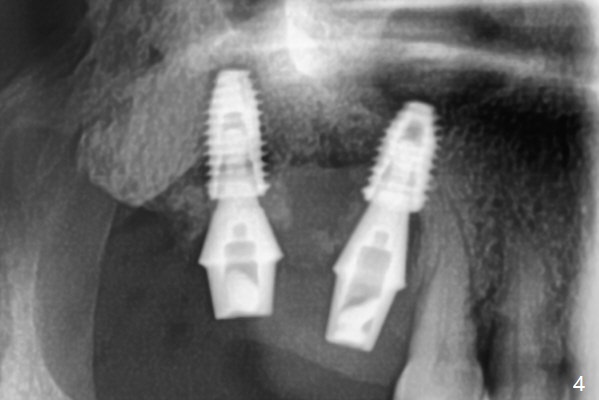

After use of 2.2 mm IS drill, DIO parallel pins are unstable at #2 and 3, partially due to shallow osteotomy. PA is not taken with parallel pins. When dummy implants are placed, the axis at #3 is noted; but instead of moving the apical end of the osteotomy distal (Fig.1 red line), the coronal end is moved mesial. By the time definitive implants and abutments are placed, the axis of #3 is parallel to that of #4, but close to each other (Fig.2,3). Orthogonal panoramic X-ray shows that they are critically close (Fig.4). If PA were taken with parallel pins after initial osteotomy, correction would be easy. The patient is doing fine postop without pain or nasal hemorrhage. There is no thread exposure 11 months postop (Fig.5). The abutment screw at #3 is retightened 7.5 months post cementation (Fig.6 (poor crown/implant ratio)).